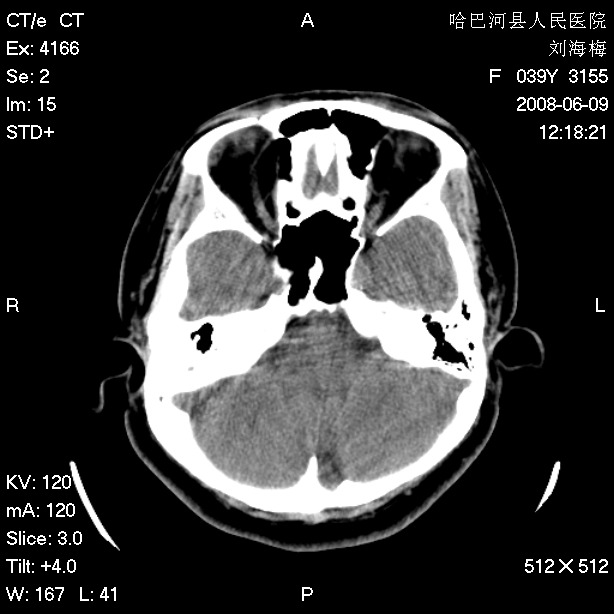

标题: CT13909:F39Y,头痛1年 [打印本页]

标题: CT13909:F39Y,头痛1年

头痛1年

枕骨皮样囊肿。

也称囊性畸胎瘤,含有中外胚层组织成分,囊壁厚,内含大量油脂、表皮、真皮及其中毛囊、皮脂腺汗腺等,常与皮肤之间有一窦道相连,也可闭合成纤维条索等。

正常变异或枕骨蛛网膜颗粒压迹。